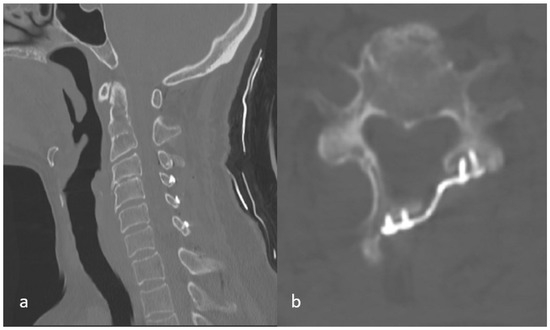

Background and Objectives: This study aimed to evaluate changes in cervical sagittal alignment after open-door laminoplasty and identify any specific preventable risk factors associated with postoperative kyphotic deformity. Materials and Methods: We retrospectively reviewed patients who underwent open-door laminoplasty for degenerative cervical stenosis between 2018 and 2021. Radiological assessment included pre- and postoperative C2–C7 Cobb angles, cervical alignment categories (lordosis, straight, sigmoid, kyphosis), and K-line status. Early postoperative CT scans were analyzed for lamina fractures and facet joint disturbances. Clinical and demographic data, as well as surgical variables such as C3 involvement, were also recorded. Results: Among 78 patients with available pre- and postoperative MRI images (mean age 56.5 ± 11.2 years; 42.3% female), the mean cervical lordosis decreased significantly from 8.78 ± 13.75° to 6.49 ± 13.82° (p = 0.024). Loss of lordosis was strongly associated with facet disturbance at the cranial-most operated level (p = 0.036), inclusion of C3 in laminoplasty (p = 0.031), and cranial-most lamina fractures (p = 0.004) in univariate analyses. However, in the multivariate logistic regression model, only the uppermost facet disturbance was identified as the independent risk factor for postoperative kyphotic change (OR 4.62, p = 0.039). C3 involvement and lamina fracture lost significance after adjustment, likely reflecting collinearity with facet injury at the cranial level. Other demographic or technical variables were not found to be statistically significant predictors. Conclusions: Postoperative sagittal alignment after laminoplasty is influenced by surgical complications at the cranial levels. A novel predictor—uppermost facet disturbance—emerged as a significant contributor to loss of lordosis. Preservation of these structures represents a practical strategy to reduce postoperative kyphotic drift. Prospective multicenter validation of the present study’s findings is warranted. Full article

Background and Objectives: This study aimed to evaluate changes in cervical sagittal alignment after open-door laminoplasty and identify any specific preventable risk factors associated with postoperative kyphotic deformity. Materials and Methods: We retrospectively reviewed patients who underwent open-door laminoplasty for degenerative cervical stenosis [...] Read more.